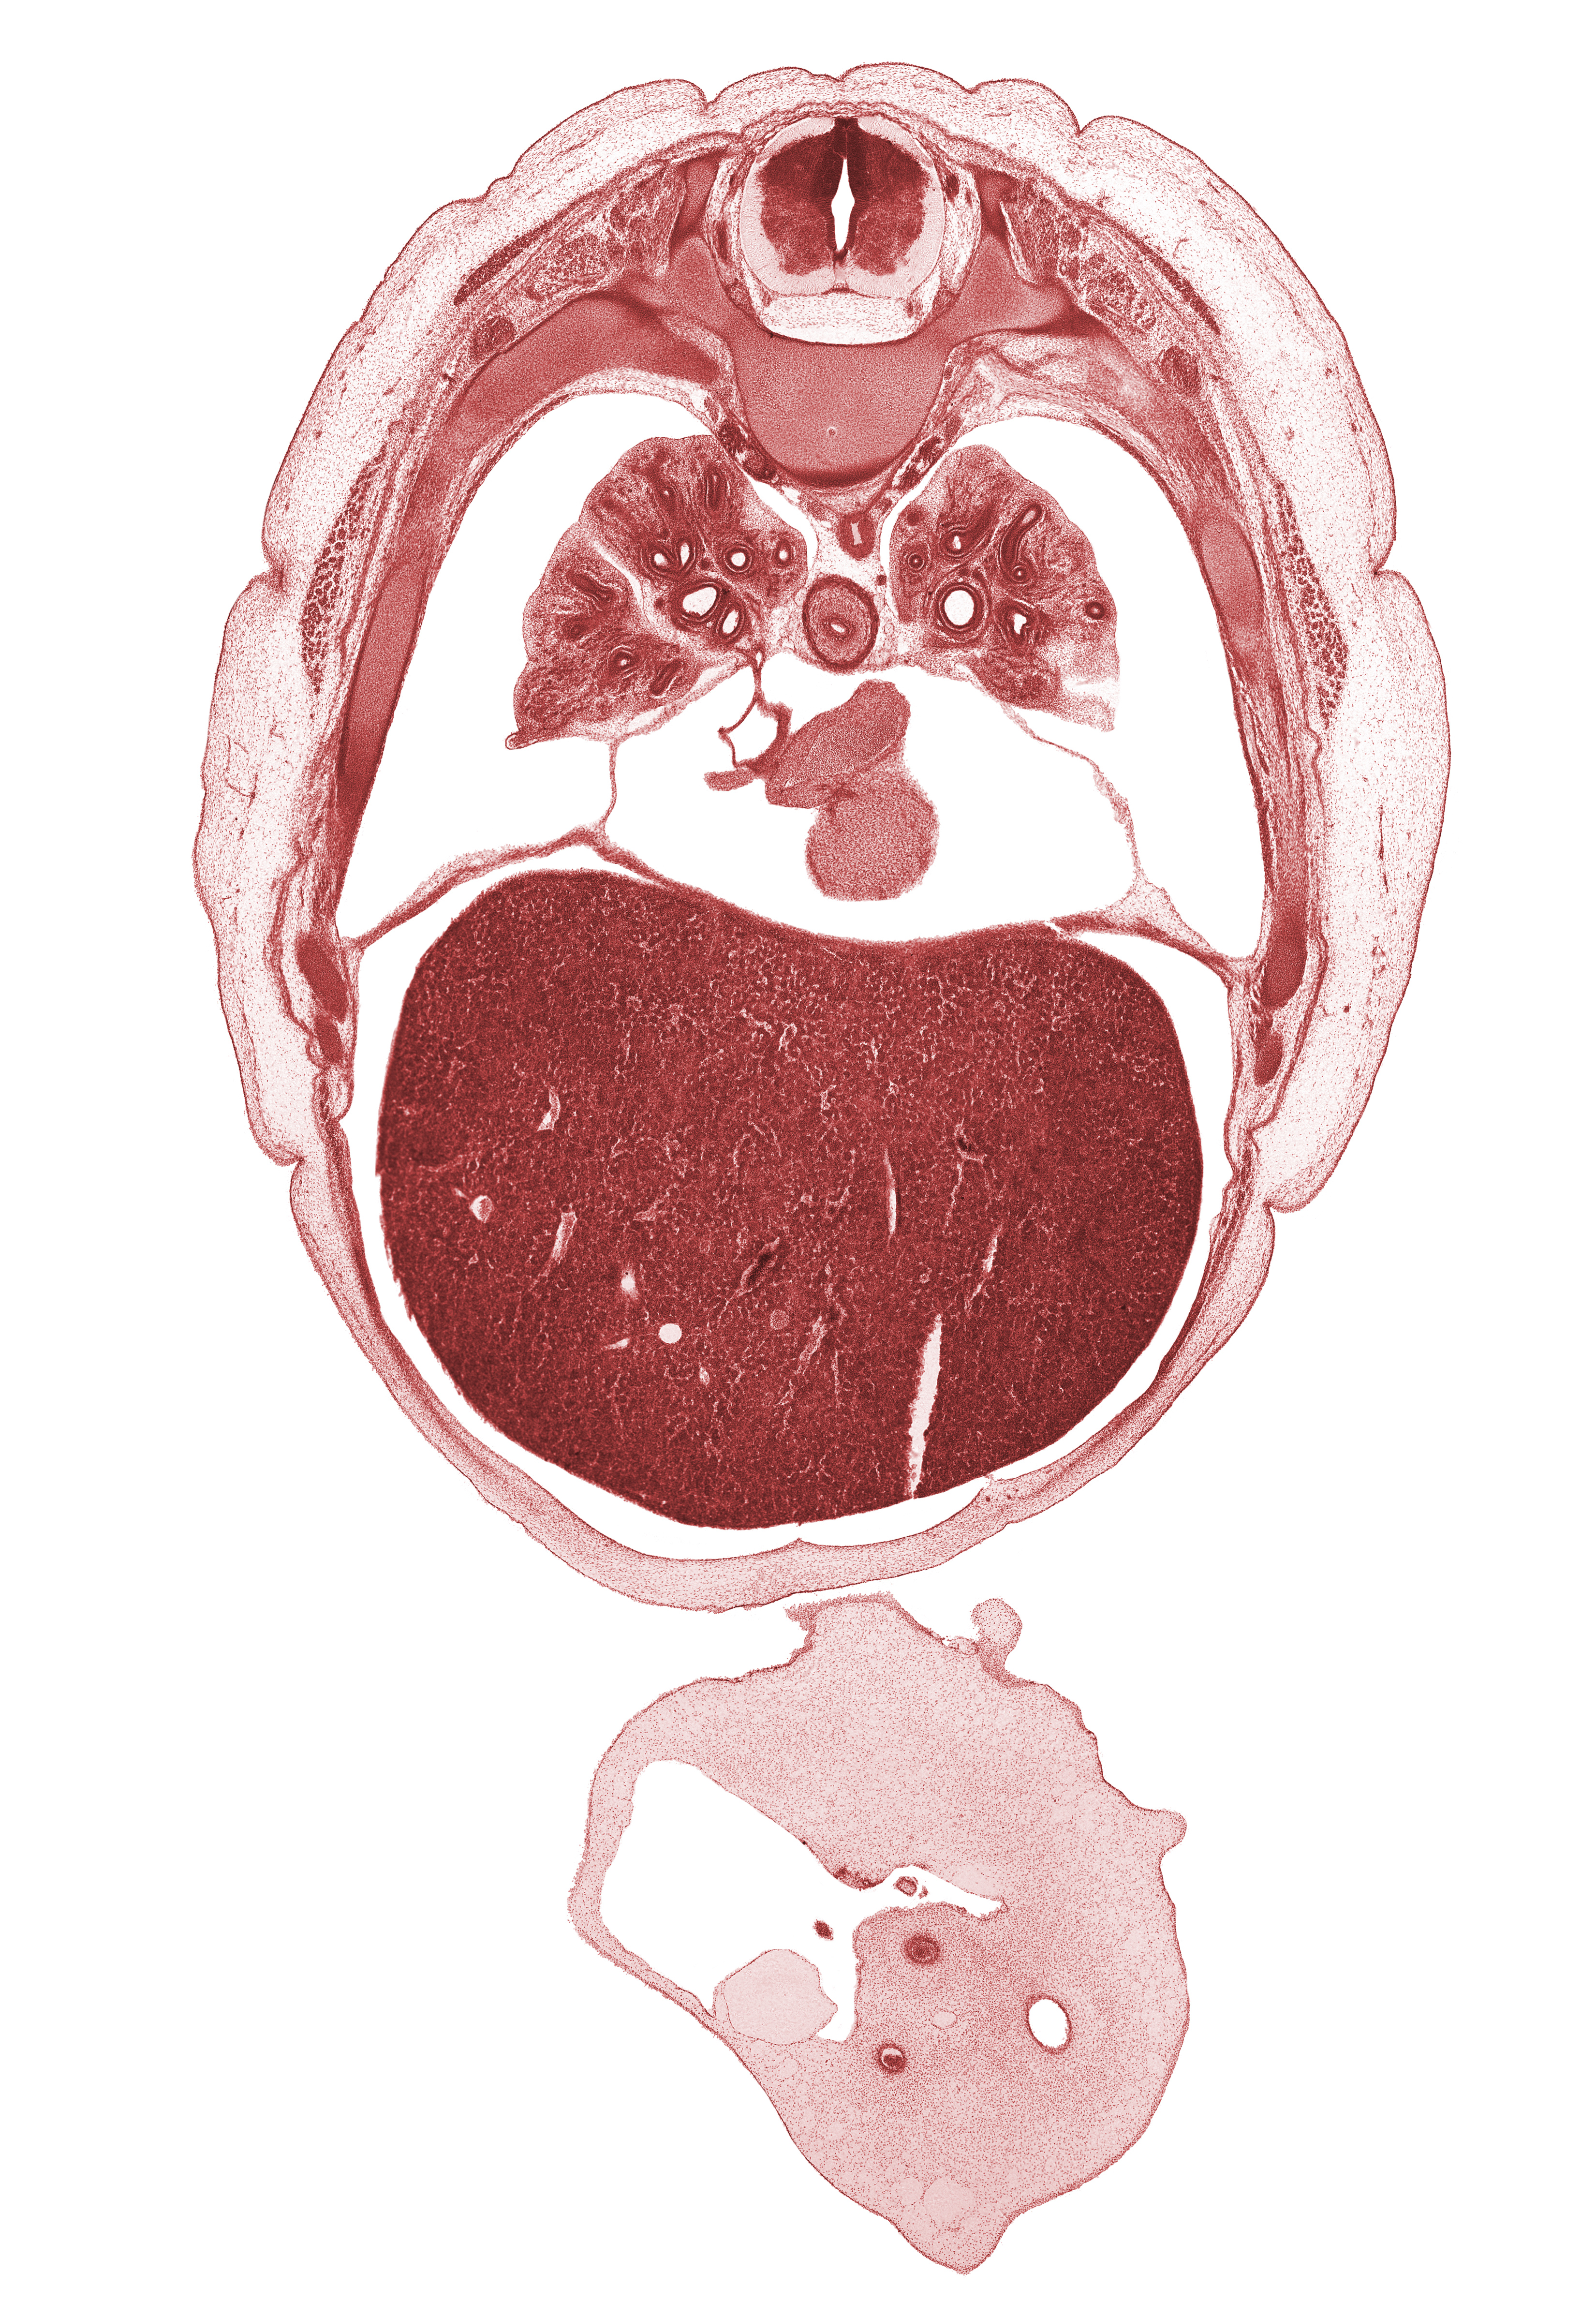

Carnegie Embryo #4090 | Location: 18-1

Keywords: L-5 ventral primary ramus, T-5 / T-6 interganglion region, T-6 intercostal nerve, allantois, caudal edge of lingula of upper lobe of left lung, external abdominal oblique muscle, inferior vena cava, left umbilical artery, left ventricle, liver prominence, lower lobe of right lung, middle lobe of right lung, oblique fissure, peritoneal cavity, rib 7, rib 8, rib 9, right atrium, right lower pulmonary vein, right umbilical artery, sympathetic trunk, umbilical coelom, umbilical vein

Source: The Virtual Human Embryo.